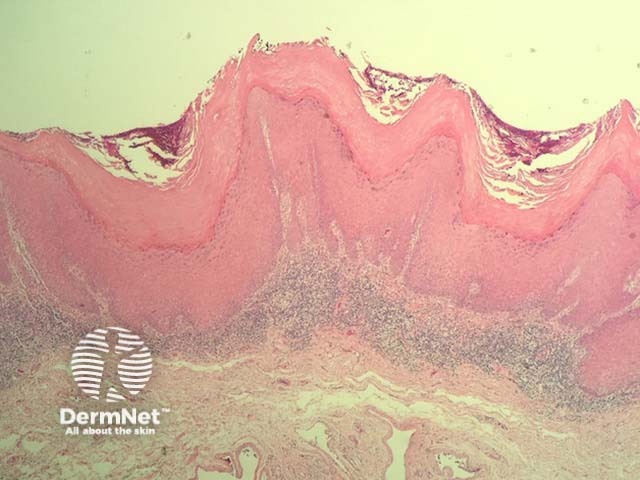

In pseudoepitheliomatous keratotic and micaceous balanitis, the histology shows acanthosis, hyperkeratosis and pseudoepitheliomatous hyperplasia with no cytological atypia (figures 1–3). There are non-specific dermal infiltrates.

Figure 1

Figure 2

Figure 3